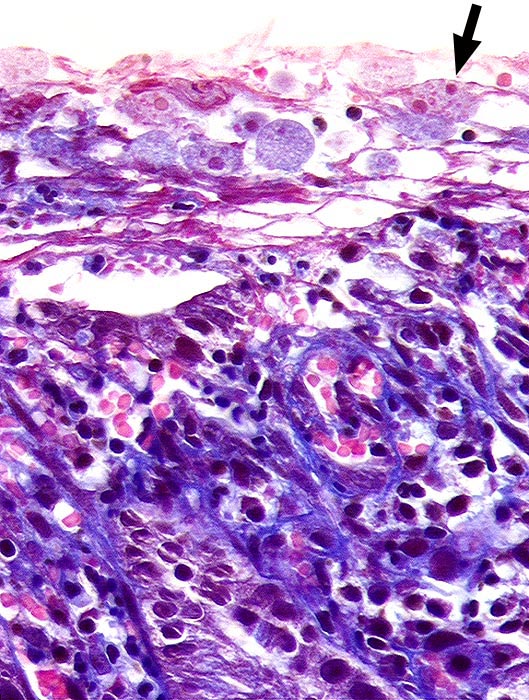

AP/ Amöbenkolitis

Amöbenkolitis

Entzündung infektiös

Darm, Anus

Kolon